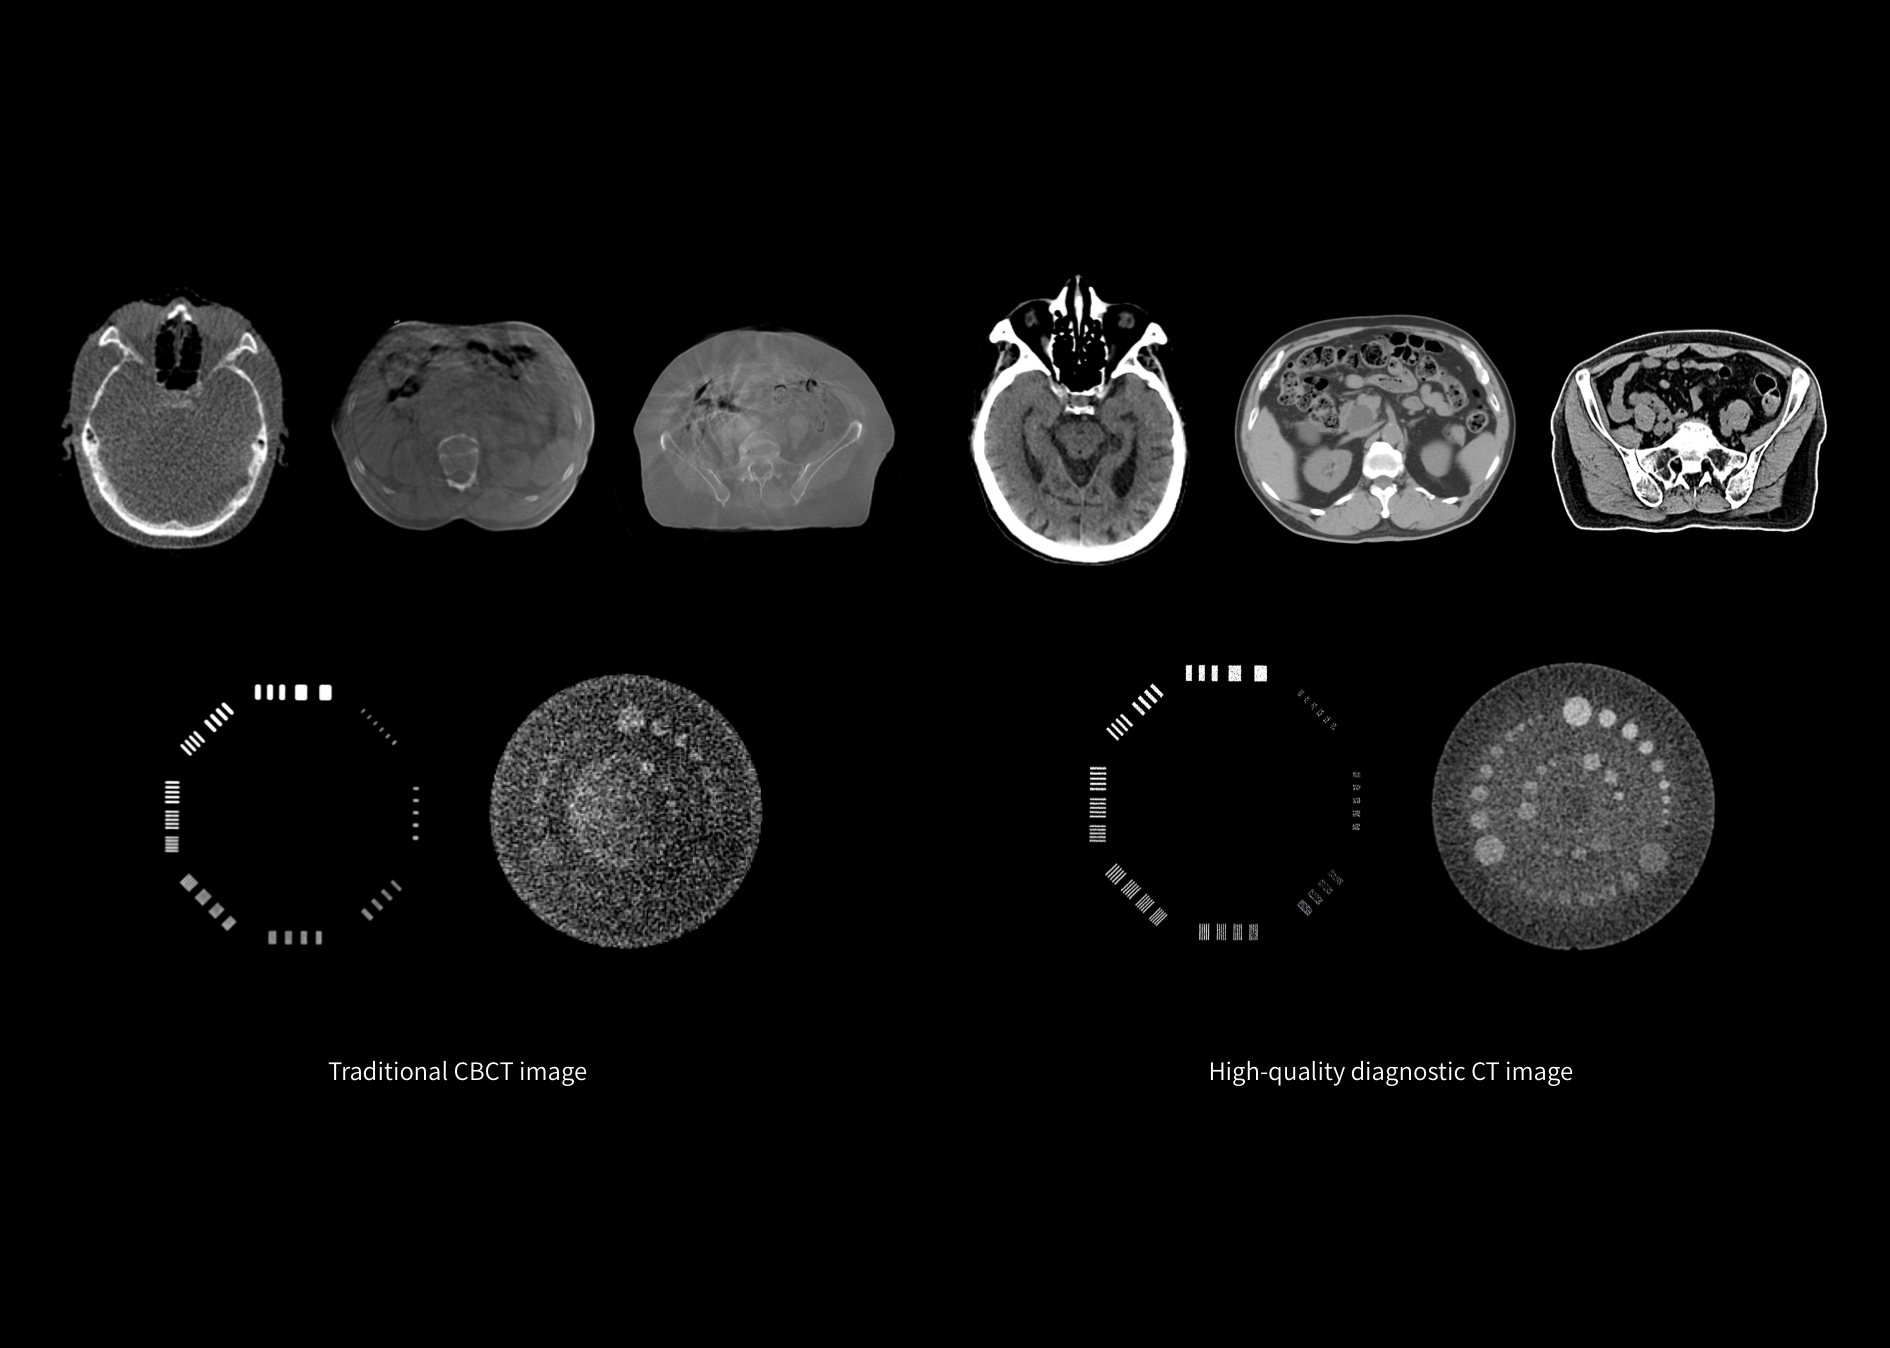

Coaxial alignment of the diagnostic CT and linear accelerator with a shared table for precise treatment. It supports the entire RT workflow from CT simulation to CT image guidance and treatment delivery.